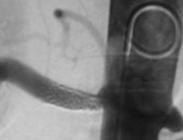

腎動脈狹窄治療

• 腎動脈狹窄

628健康網為您分享有關腎動脈狹窄的癥狀,腎動脈狹窄的治療方法,腎動脈狹窄的預防知識,腎動脈狹窄的癥狀圖片,腎動脈狹窄...